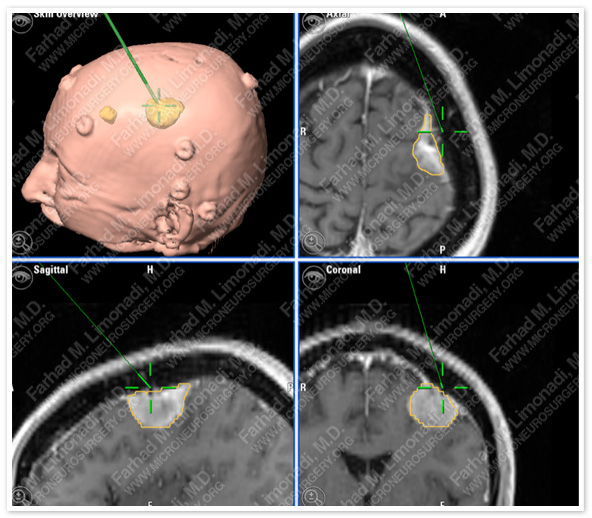

MRI scan of the patient’s brain shows a dural based tumor in the left frontoparietal convexity overlying the motor strip.

Computer Navigation

Stereotactic and computer navigation was used to determine the precise location of the tumor (outlined in yellow). She had a second benign tumor in front the symptomatic one which was treated conservatively as patient was not symptomatic with it.